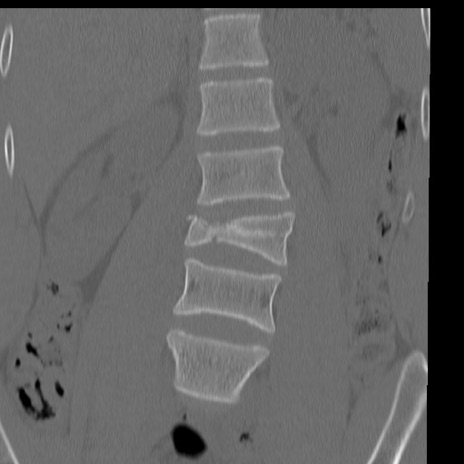

症例3 腰椎CT(冠状断像)

腰椎CT

矢状断像